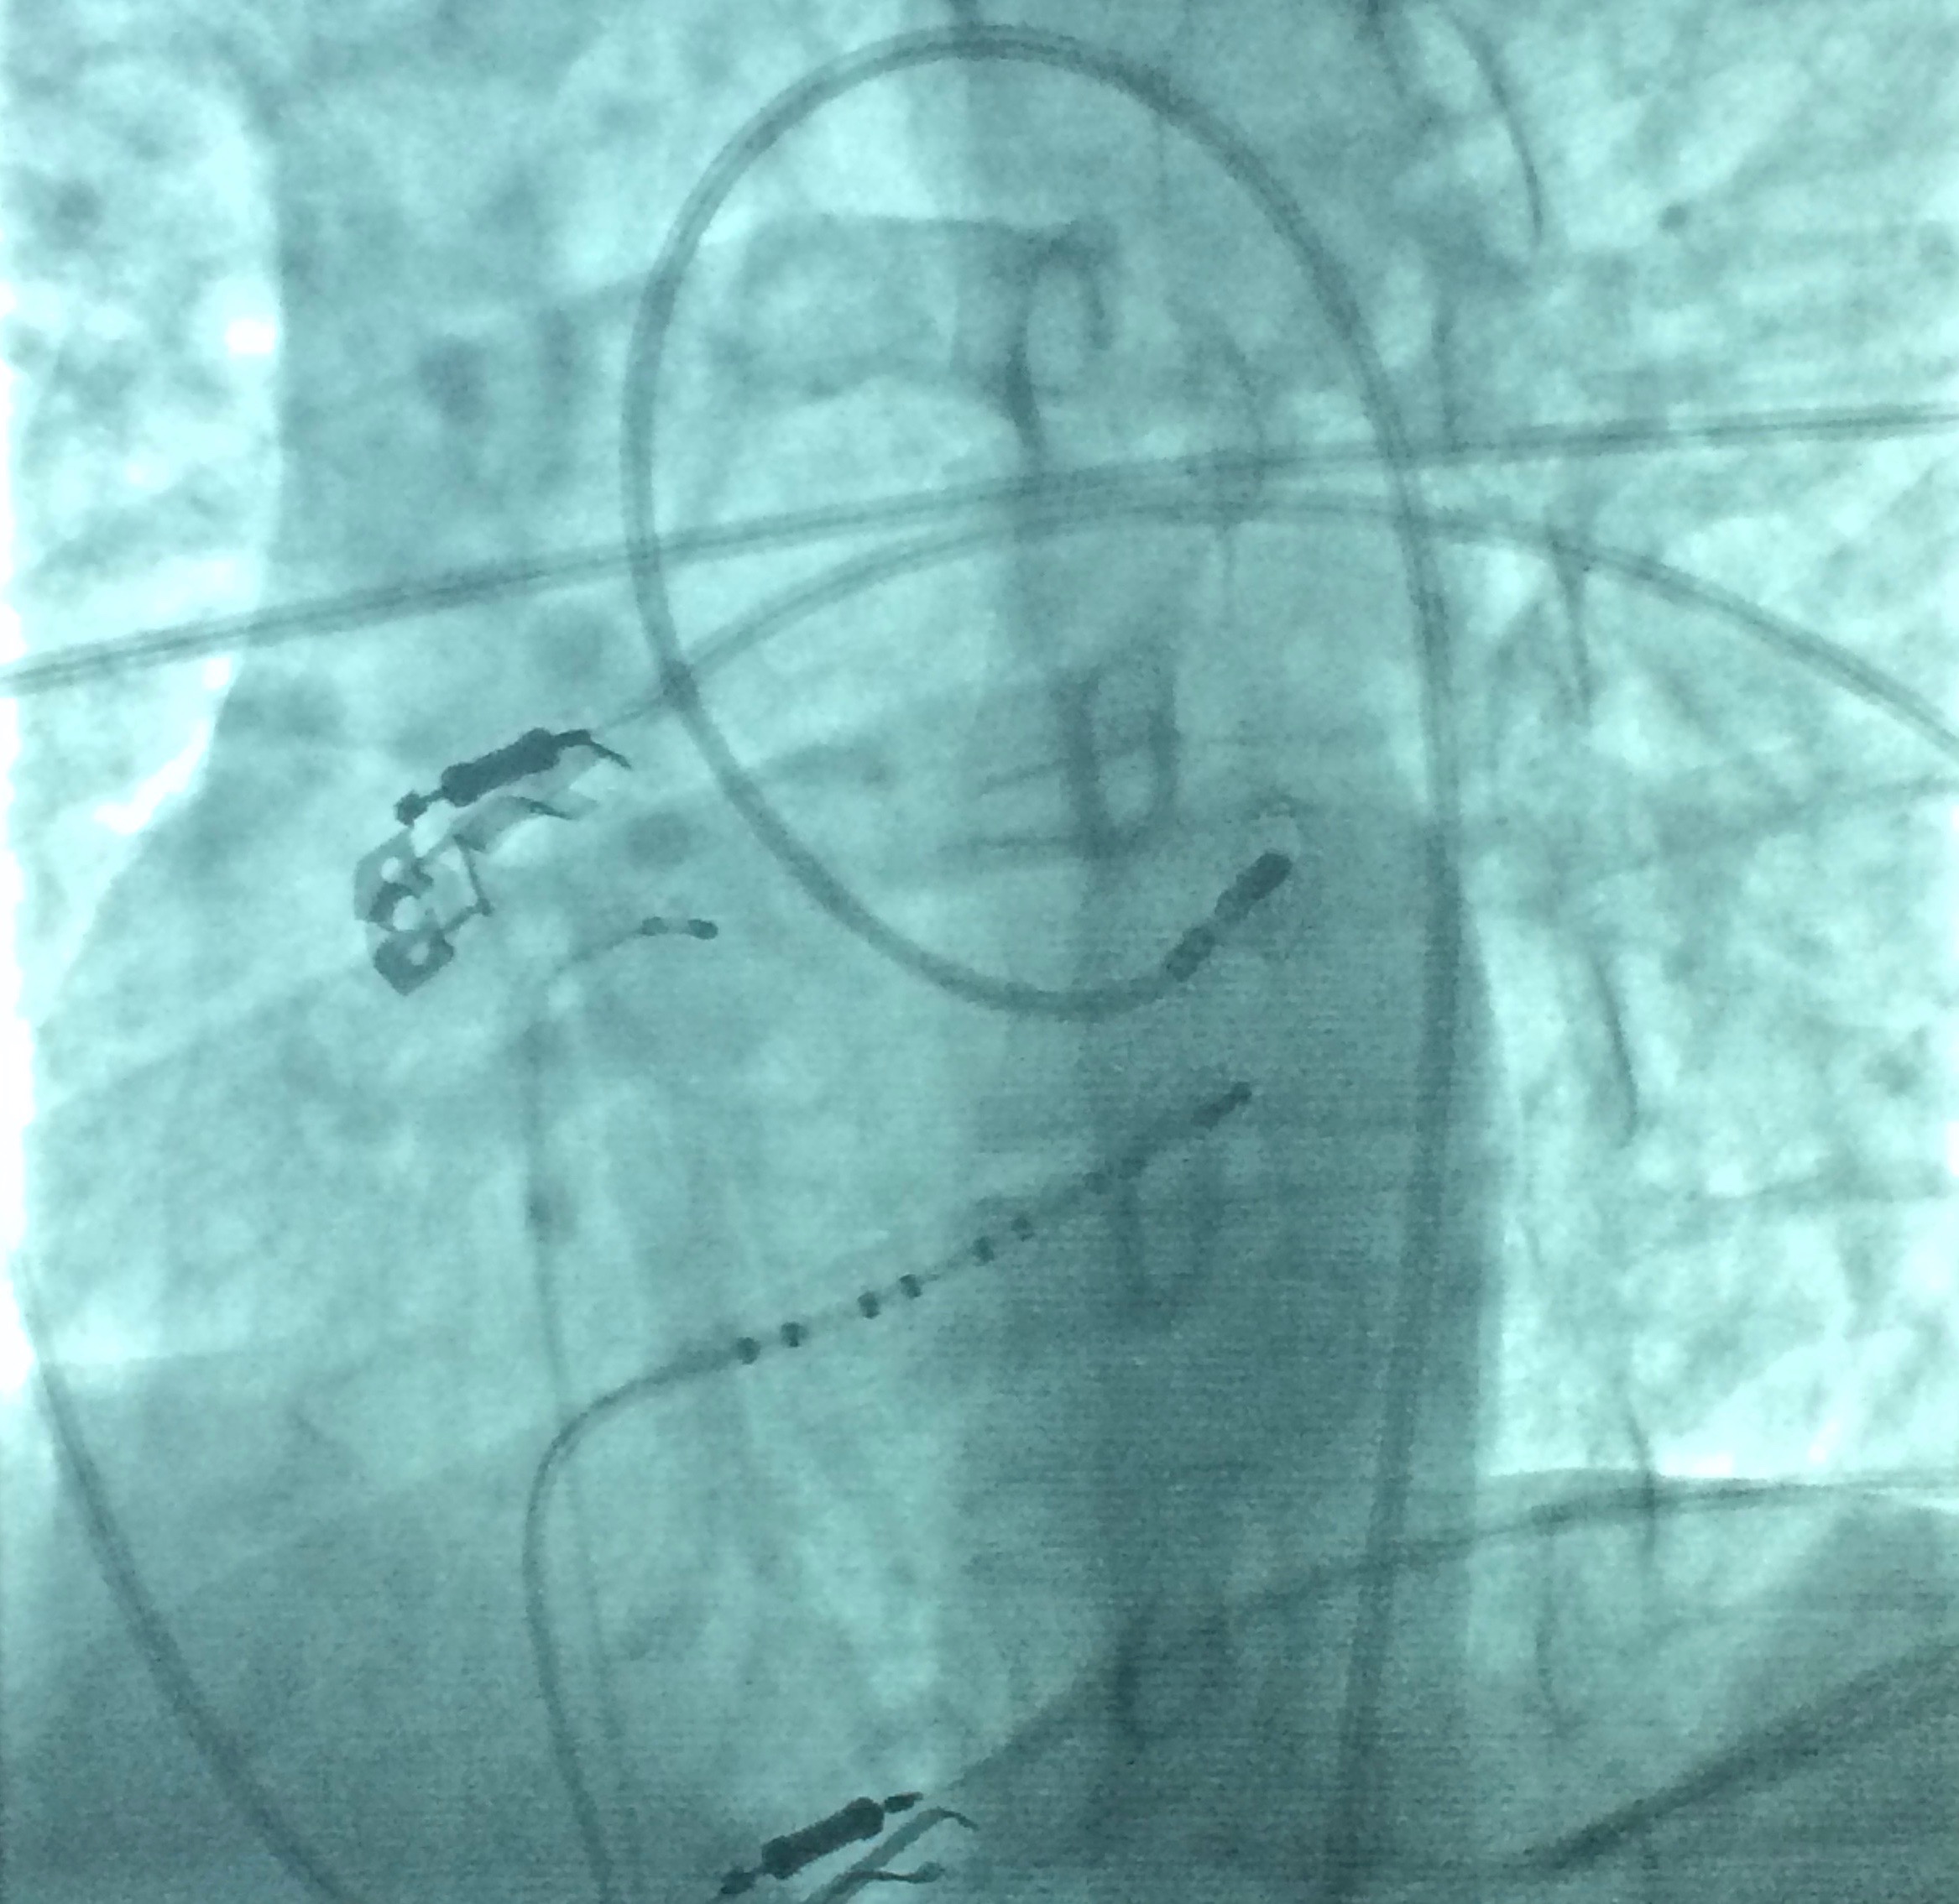

De son côté, l'Open Heart à fourni Cathlab avec l'équipement X-ray adéquat, un cardiologue local ayant un intérêt pour la Rythmologie/EP, un système de stérilisation (ETO) pour câbles et cathéters, des sets de ponction ainsi qu'une base de données.

La phase initiale du projet fut riche en enseignements. La première session EP + ablation EP se déroula du 20 au 24 septembre 2015 par Dr. Marc Zimmermann et Mr Lionel Agnoletti